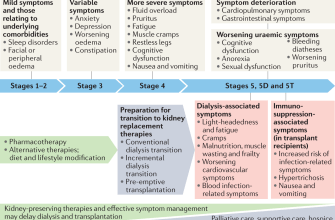

Kidney disease, also known as renal disease, is a condition

Kidney dysfunction, also known as renal dysfunction

Kidney problems can have a significant impact on overall